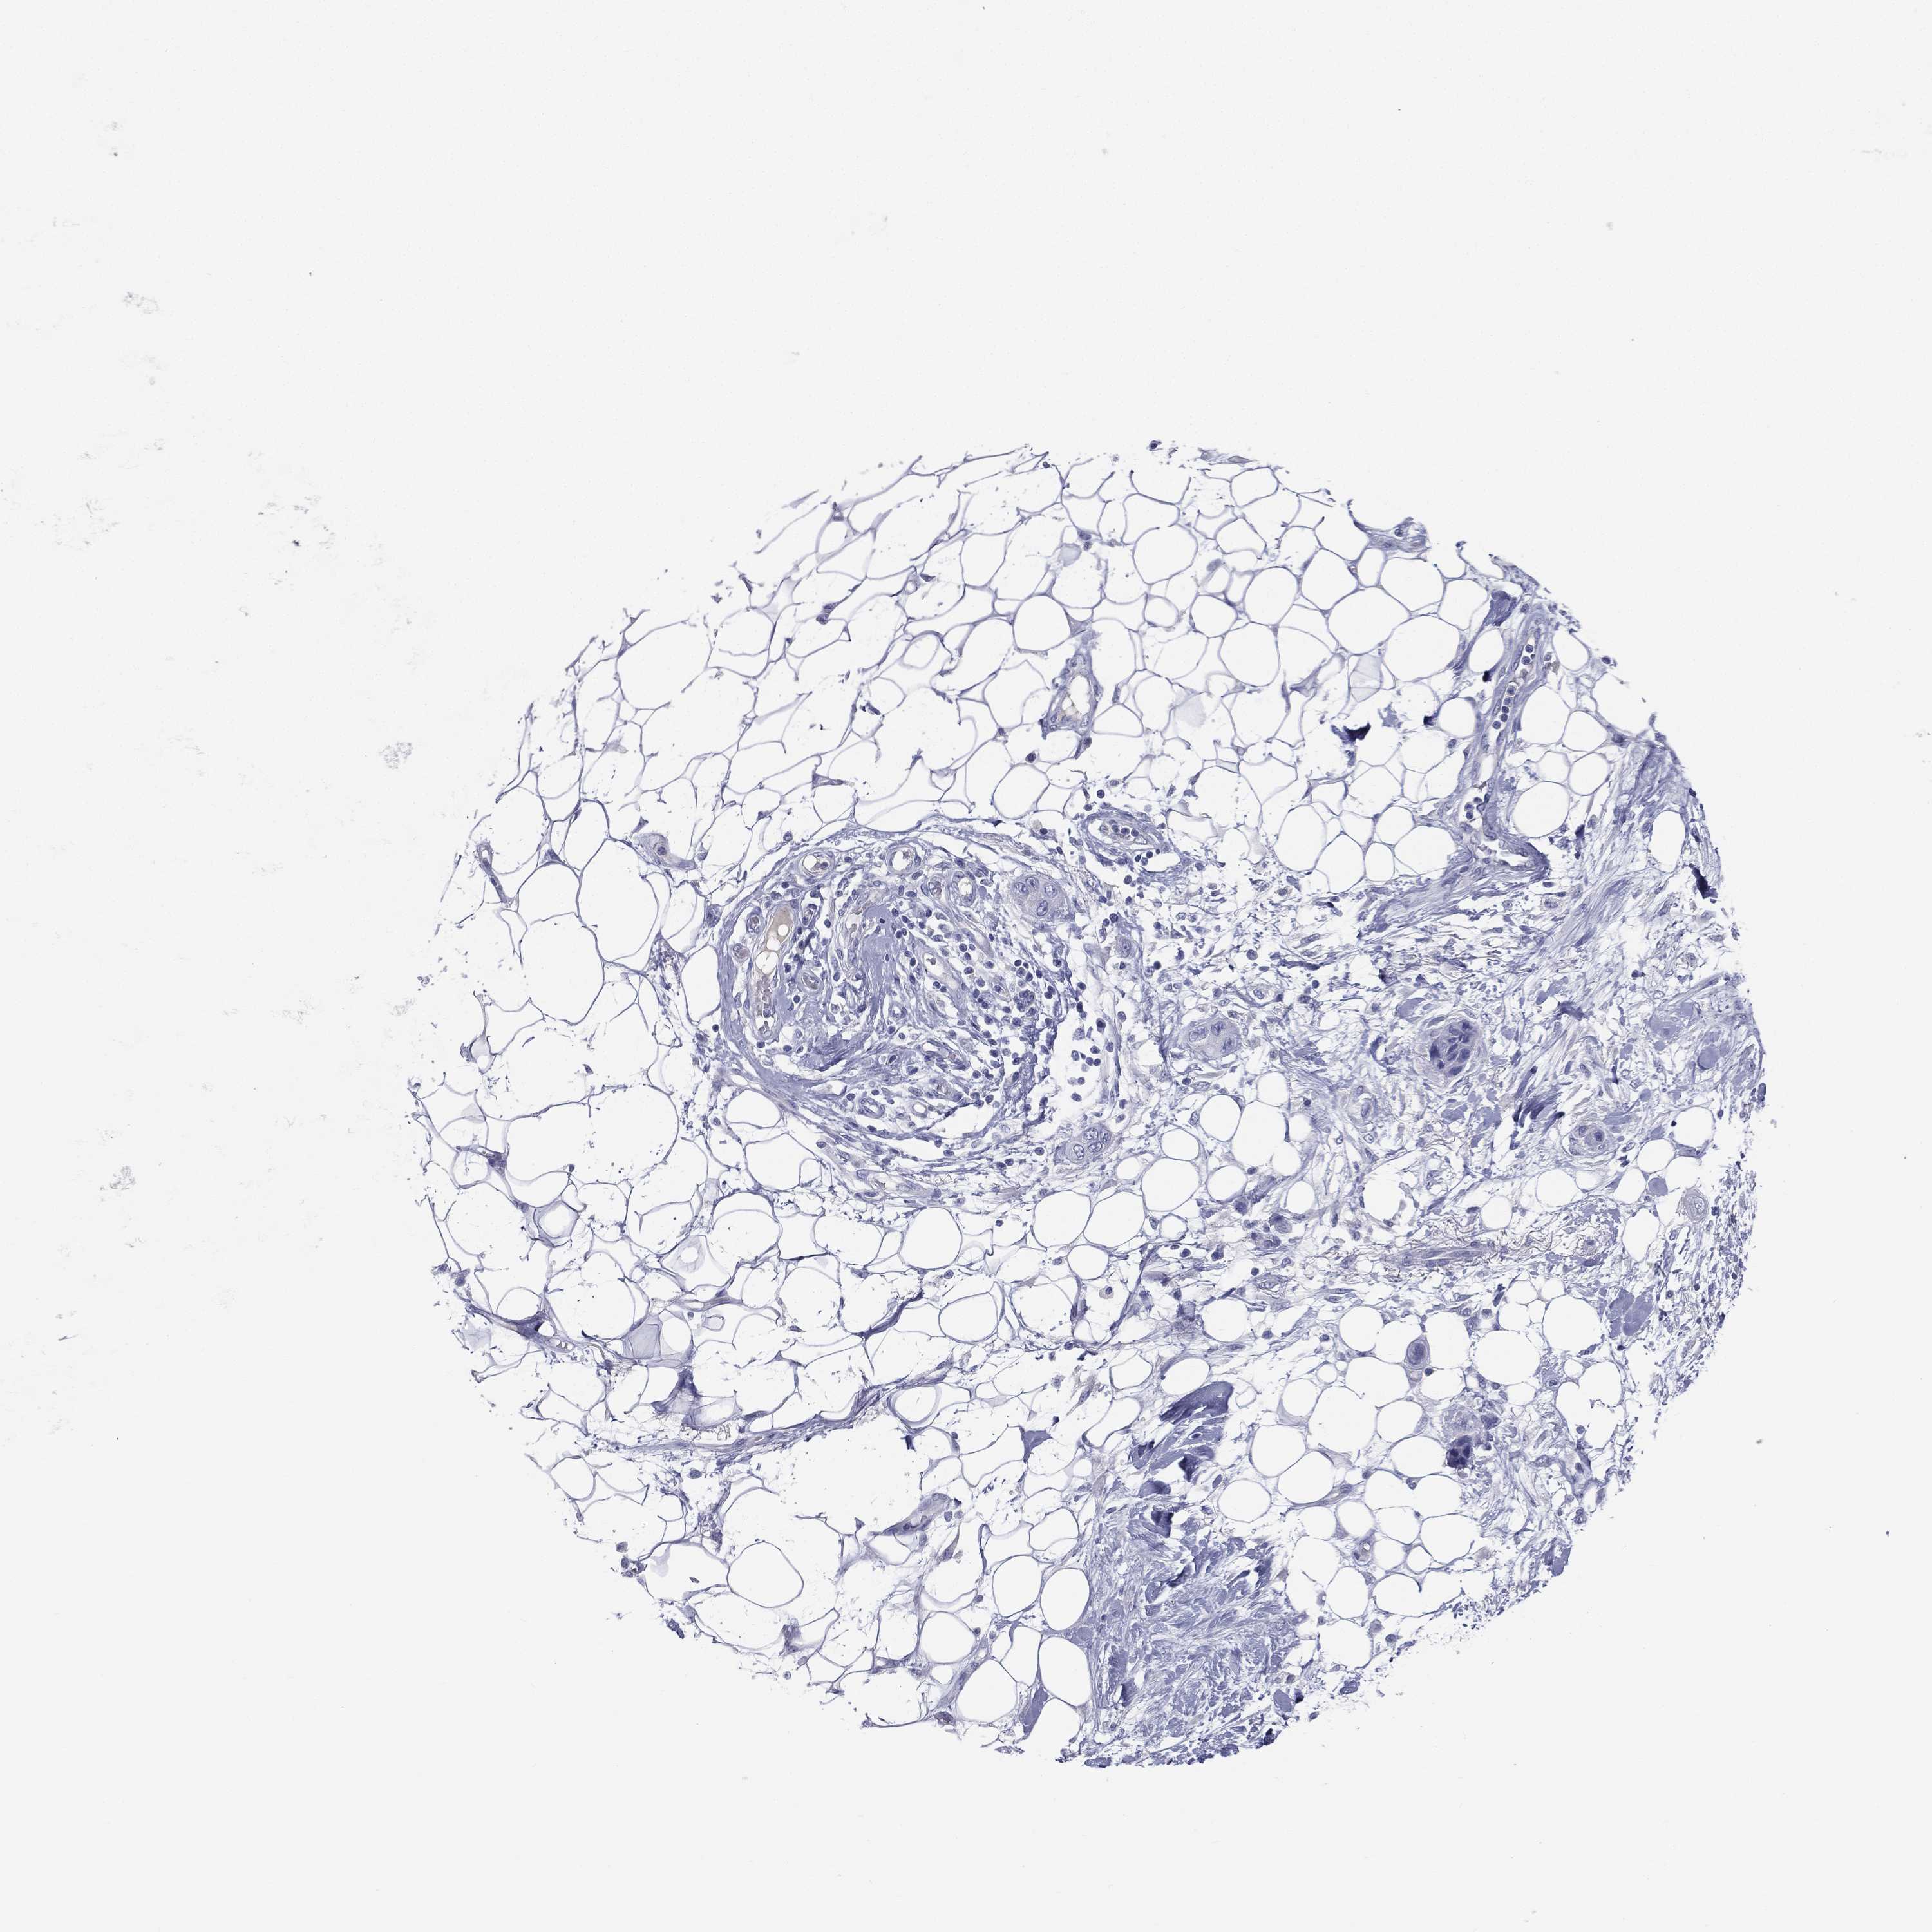

Basal cell and squamous cell cancer

SKIN CANCER - Protein expressioni

A mouse-over function shows sample information and annotation data. Click on an image to view it in a full screen mode. Samples can be filtered based on level of antibody staining by selecting one or several of the following categories: high, medium, low and not detected. The assay and annotation is described here.

Antibody stainingi

Antibody staining in the annotated cell types in the current human tissue is reported as not detected, low, medium, or high, based on conventional immunohistochemistry profiling in selected tissues. This score is based on the combination of the staining intensity and fraction of stained cells.

Each image is clickable and will lead to virtual microscopy that enables deeper exploration of all samples and also displays staining intensity scores, fraction scores and subcellular localization as well as patient and tissue information for each sample.

Antibody HPA002904

Staining

High

Medium

Low

Not detected

Intensity

Strong

Moderate

Weak

Negative

Quantity

>75%

75%-25%

<25%

None

Location

Nuclear

Cytoplasmic/membranous

Cytoplasmic/membranous,nuclear

Basal cell carcinoma

Squamous cell carcinoma, NOS